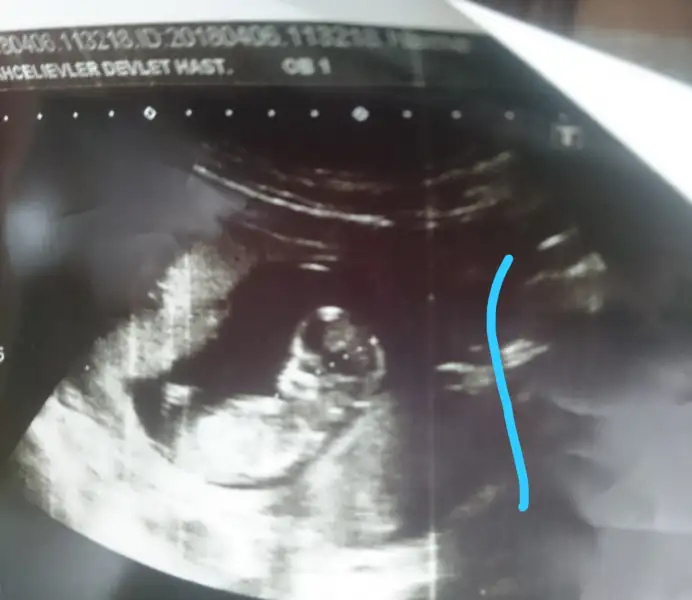

Nuchal translucency 1.00 mm yazıyo bu mu bilmiyorum nt dedikleri şey .İnce mi demek oluyo bilmem

Kıza benziyor canım

Kiz gibi geldi bana

Kiza benzettim ben canimKızlar benim bebeğime de tahmin de bulunabilir misiniz ??

Erkek bence

Doktor bi kız bi erkek dedi bakalimErkek bence)

Kızlar bebeğimin ense kalınlığı 2,4 çıktı. Doktor genellikle 1 ve 1,5 arası olmasını isteriz dedi. Kan sonucuna göre daha sağlıklı yorum yapılacakmış . Kan sonucumuda 2 hafta sonra çıkacak